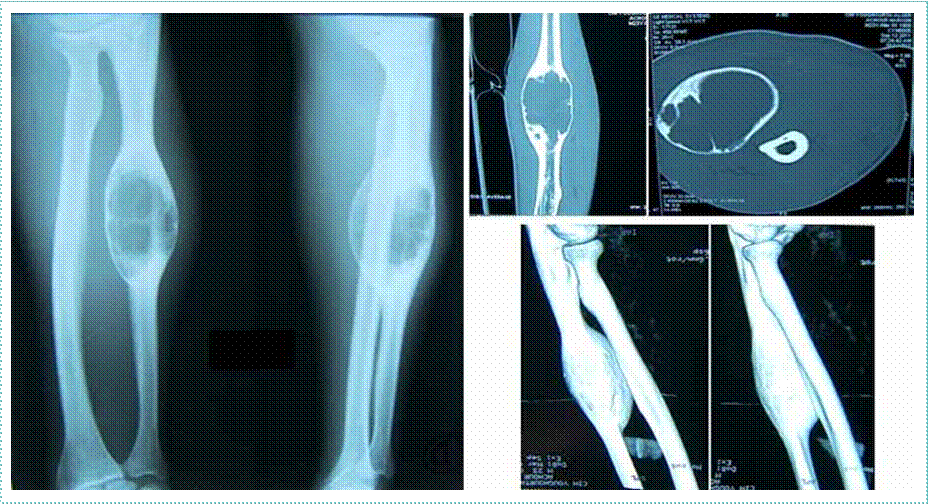

• IRM cérébrale et médullaire :

L’IRM cérébrale de début répondait aux critères de Barkhof chez 119 patients soit 94%. L’IRM médullaire faite chez 49 patients a montré des anomalies chez 35 patients (71%), et était normale chez 14 patients (29%). L’IRM cérébrale de contrôle réalisée 03 mois après l’IRM de référence faite chez 101 patients a

confirmé la dissémination temporelle chez 55 patients (54,45%), avec l’apparition de nouvelles lésions T2 chez 39 patients (38%) avec de nouvelles lésions actives chez 26 patients (25%).

Dans notre étude, aucune association n’a été retrouvée entre l’âge, le sexe, la présence de BOC et la survenue d’un 2ème événement clinique. Alroughani et al. [23] ont rapporté que l’âge de début jeune était un facteur prédictif de la survenue d’un 2ème événement dans les 2 ans. Concernant la présence de BOC, aucune différence significative n’a été retrouvée entre la présence ou l’absence de BOC et le délai de survenue d’un 2ème événement dans 2 études récentes [20,21]. Beghdadi [15] a retrouvé dans son étude que tous les paramètres IRM (le nombre de lésions T2, la topographie et l’activité lésionnelle), avaient une valeur prédictive positive dans la conversion du SCI en SEP selon les critères de Mc Donald, augmentant significativement le risque d’une deuxième poussée. De ce fait, l’IRM est actuellement l’outil le plus puissant pour prédire la conversion en SEP cliniquement définie [34].

Dans notre travail comme dans l’étude de Beghdadi [15], l’IRM cérébrale de début était pathologique dans tous les cas et répondait aux critères de Barkhof chez 94% des patients. Un peu plus de la moitié de nos patients (54,45%) se sont convertis en SEP radiologique à leur 2ème IRM de contrôle réalisée 3 mois après l’IRM de référence, dont 38% avaient de nouvelles lésions T2 et 25% avaient de nouvelles lésions rehaussées après injection de gadolinium.